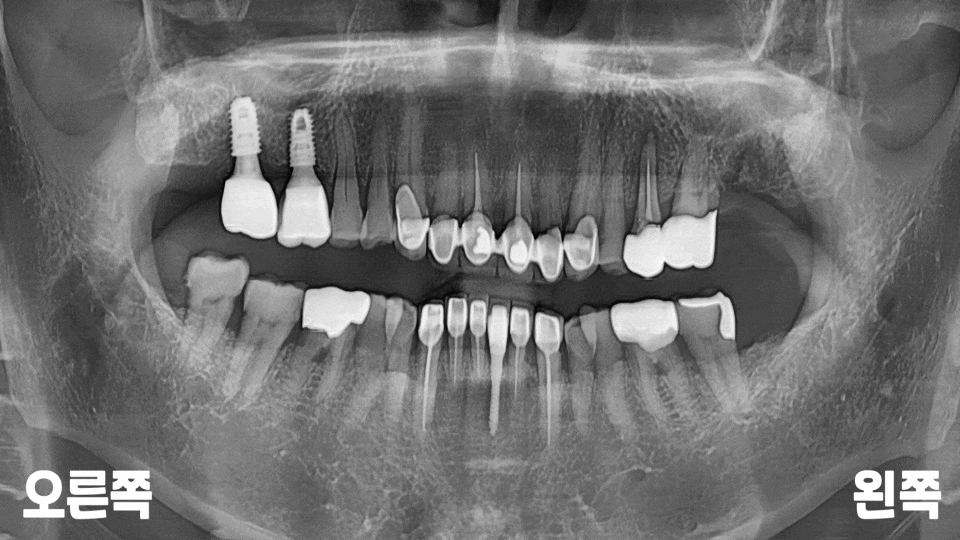

모든 임플란트 마무리 후에

확인을 위한 파노라마를

추가로 촬영해 보았습니다.

위아래로 교합 라인도

턱지지 않고 잘 맞고,

씹을 때도 높지 않고

편안하다고 해주셨는데요.

앞으로 정기적인

6개월~1년 검진을 통해

불편한 점이 있는지

계속 관리해 드릴

예정입니다.